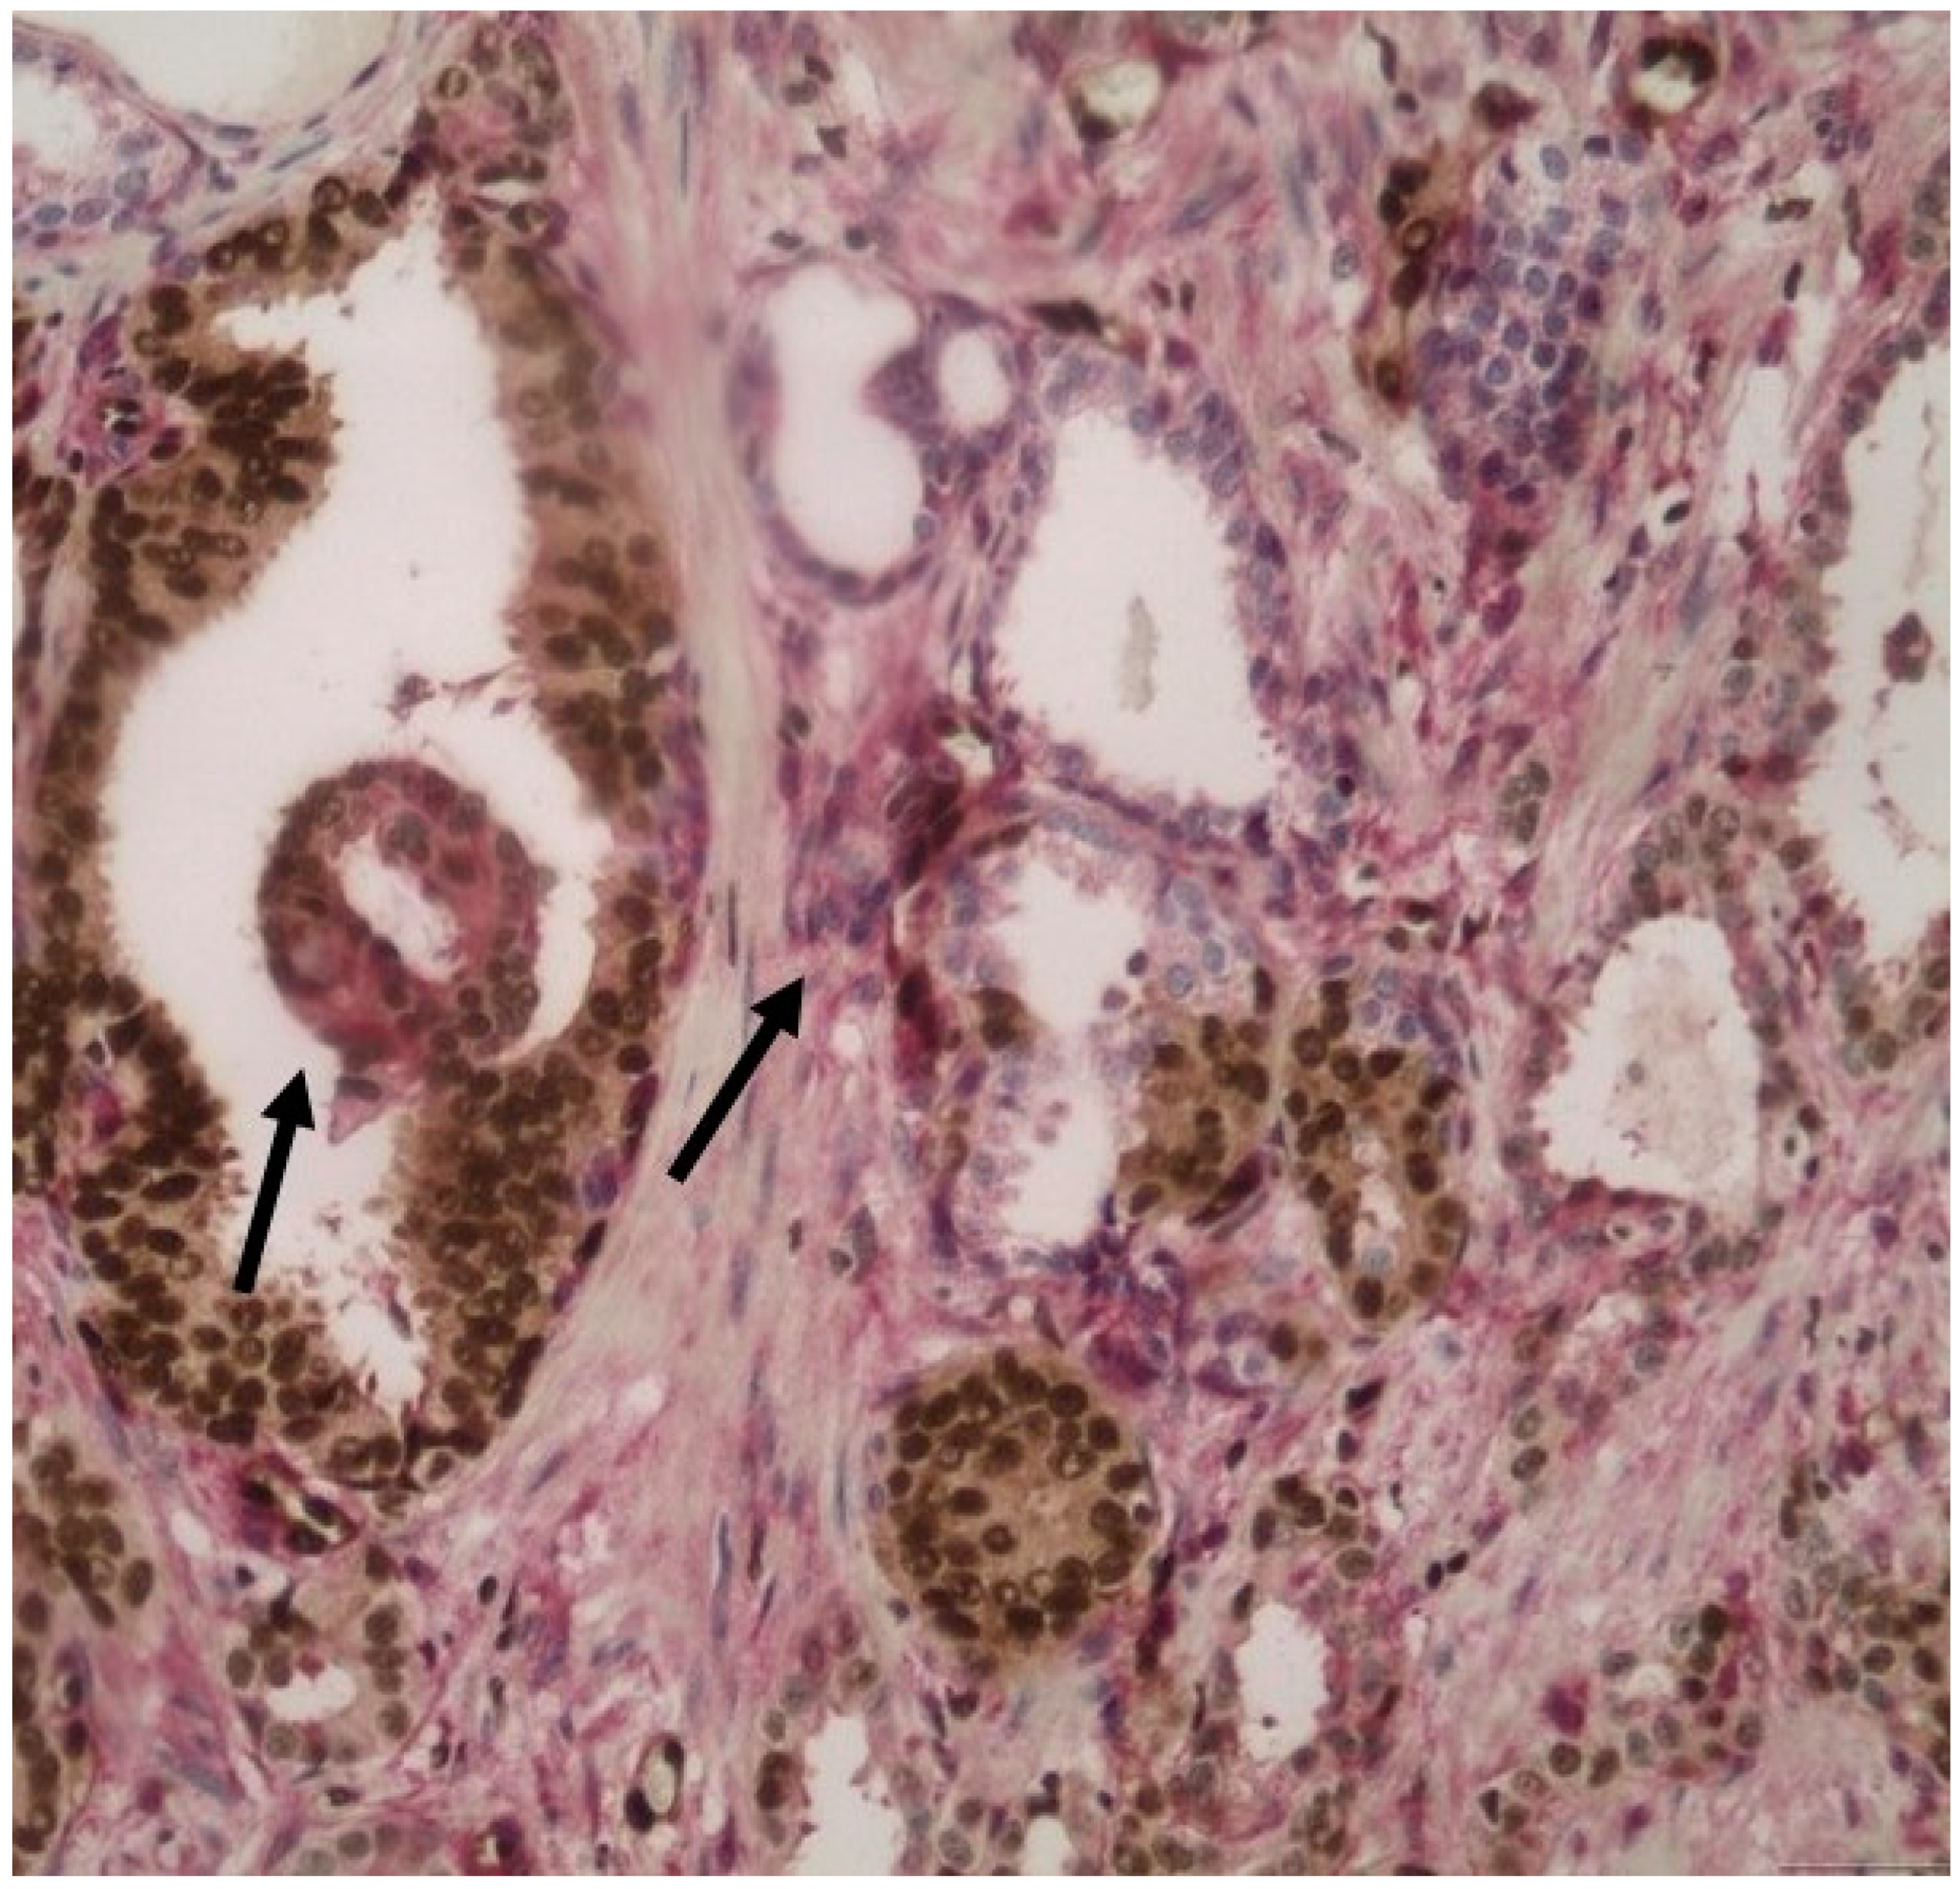

3.3. PTEN Expression in HGPIN and Its Association with the Adjacent Invasive Prostate Cancer

3.4. ERG Expression in IDCP and Its Association with the Adjacent Invasive Prostate Carcinoma